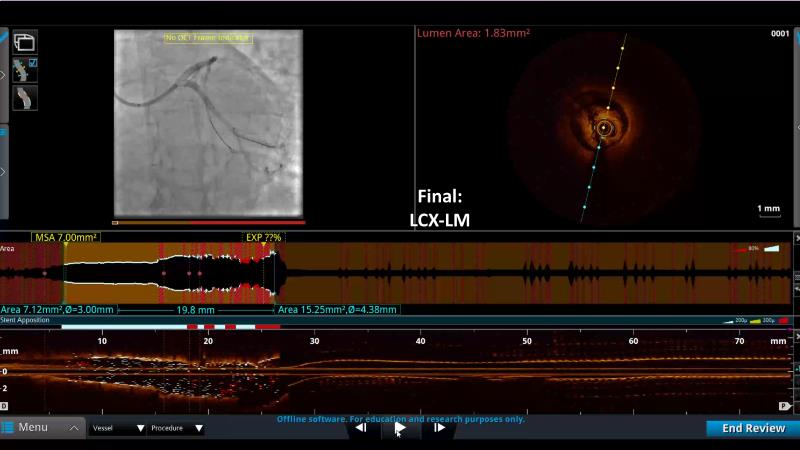

- To define the use of OCT in PCI of complex coronary lesions